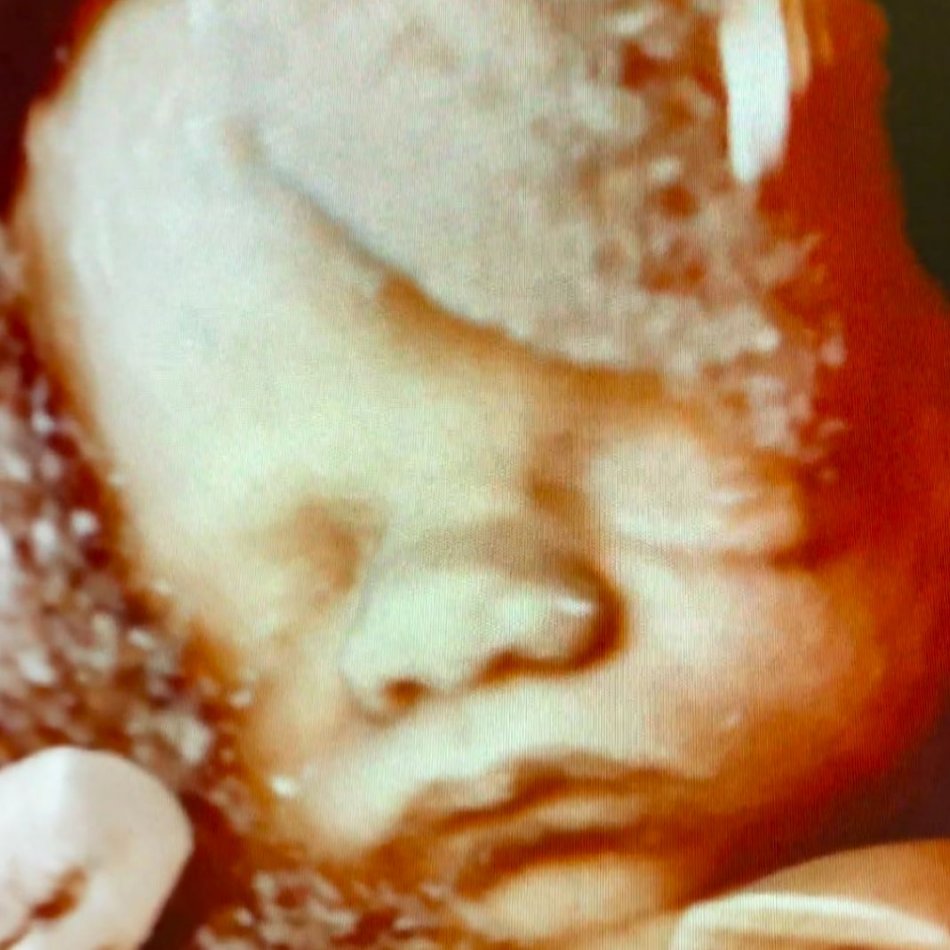

Galéria k článku NAJMODERNEJŠIE vyšetrenie pre budúce mamičky: Odhalí ZÁVAŽNÉ ochorenia a aj bez PRIPLÁCANIA

Zdroj: FNsP F. D. Roosevelta